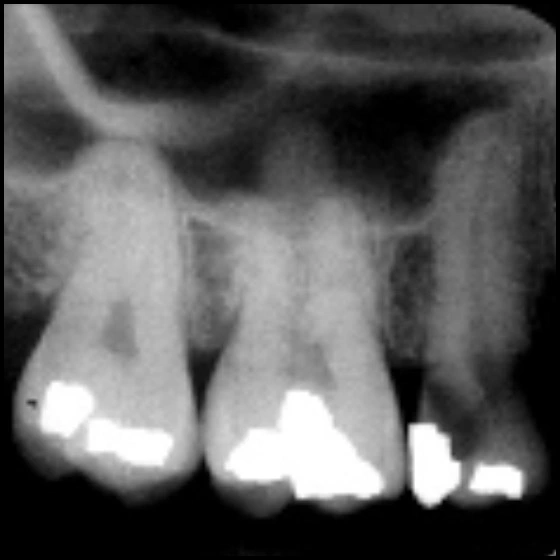

The bitewing radiographic image is used to examine the interproximal surfaces of the teeth and is particularly useful for the detection of dental caries and the evaluation of alveolar bone levels. The intraoral technique provides high spatial resolution imaging of teeth and. Intraoral radiographs still remain one of the most important imaging modalities available in dentistry to the dental practitioner. • describe the standard for image orientation, arrangement and viewing of intraoral radiographic images. Intraoral imaging techniques provide superior image resolution, allowing the detection of earlier and less apparent changes. A radiographic survey of the whole mouth intended to display the crowns and roots of all teeth, periapical areas,. All three modalities are available for use. Intraoral radiographic images can be acquired with digital receptors or radiographic film. • discuss the typical anatomic structures.